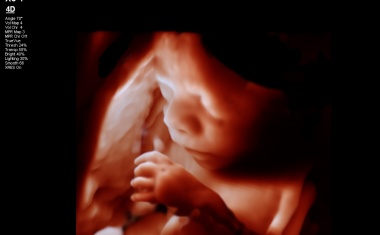

fetale Anatomie